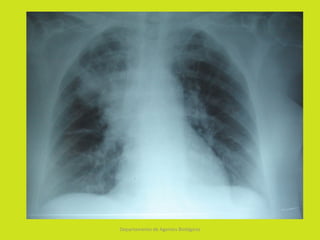

NEUMOLOGÍA

•   Neumonía necrosante

•   Neumonía de comienzo súbito

•   Neumonía en focos múltiples

•   Formación de Neumatoceles – Neumotórax

•   Empiema es complicación frecuente.

•   Neumonía Grave en menores de 12 meses.

Neumonía necrosante • Neumonía de comienzo súbito • Neumonía en focos múltiples • Formación de Neumatoceles – Neumotórax • Empiema es complicación frecuente. • Neumonía Grave en menores de 12 meses. Departamento de Agentes Biológicos